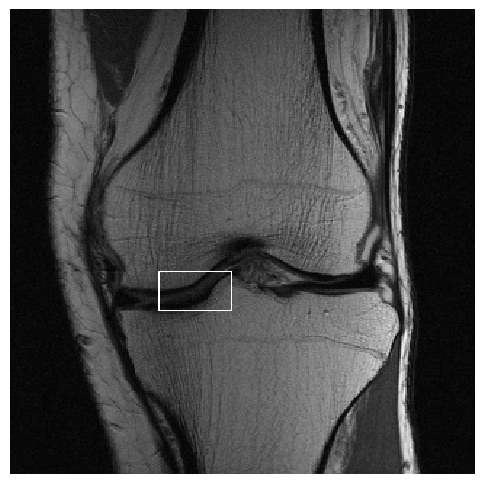

Figure 3: Reconstructions results. Rows 1 and 3: Examples of comparing the ground truth (GT) fully sampled image to the reconstructed images obtained by the three models (1-3), NPB-REC, baseline, E2E-VarNet trained with Dropout, and the NPB-REC std. map at accelerations R=4𝑅4R=4, R=8𝑅8R=8, respectively. Rows 2 and 4: The corresponding annotated ROIS of Nonspecific white matter lesions.

Fig. 3 presents examples of reconstruction results obtained by (1) our NPB-REC approach, (2) the baseline, and (3) Monte Carlo Dropout, for equispaced masks with two different acceleration rates R=4𝑅4R=4 and R=8𝑅8R=8. The reconstructed images predicted by the three models are smoother than the reference image. This is due to the fact that all the models were trained with SSIM loss, which tends to produce overly smooth reconstructions while preserving the diagnostic content and the anatomical features Sriram et al. (2020a). These images can be enhanced by dithering the image by adding a small amount of random Gaussian noise to produce a more textured reconstruction, as proposed in Sriram et al. (2020b).

Table 1 presents the mean PSNR and SSIM metrics, calculated over the whole inference set, for the three models. Our NPB-REC approach achieved significant improvements over the other methods in terms of PSNR and SSIM (Wilcoxon signed-rank test, pmuch-less-than\ll1e-4, except for SSIM values in line W, R=4𝑅4R=4 where they are roughly the same for NPB-REC and Baseline). The improvement in the reconstruction performance can be noted both quantitatively from the metrics, especially for masks with acceleration rate R=8𝑅8R=8, and qualitatively via the images of annotations, where our results show less smoothness than those obtained by Dropout.